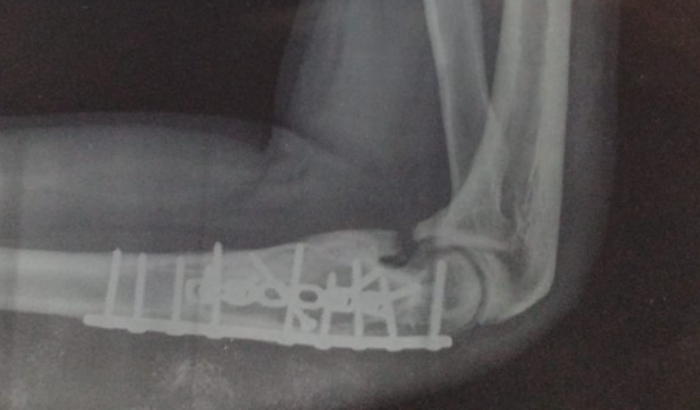

Olá, eu sou o Jeanderson, fraturei o Úmero e preciso retirar um calo Ósseo, por amor me ajude nesse objetivo, vai mudar a minha vida! ver tudo

Olá, eu sou o Jeanderson, fraturei o Úmero e preciso retirar um calo Ósseo, por amor me ajude nesse objetivo, vai mudar a minha vida!